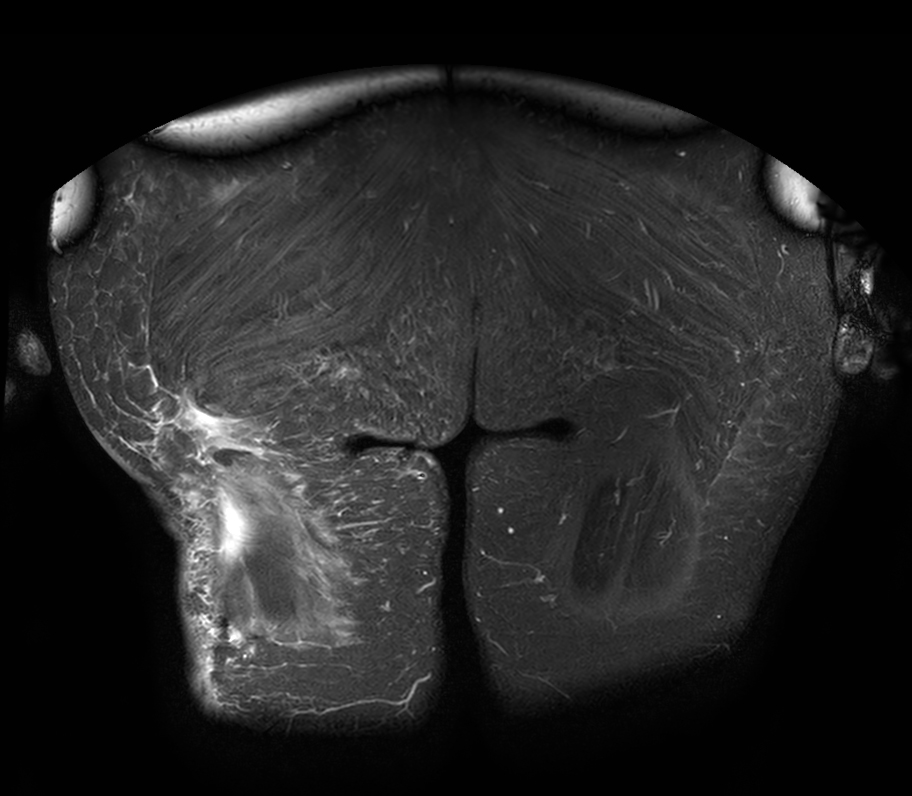

Coronal STIR